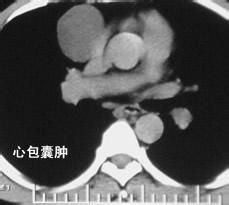

病變可發生於心包任何部分,甚至在上縱隔心臟基底部,但以右側心膈角最常見,囊腫大小不一,薄而透明,囊內液體澄清如水或為淡黃色透明液,液體量一般在30ml以內,少數可達1000ml,其結構為單房或多房性囊壁,外壁為疏鬆結締組織,內壁為單層的間皮或內皮細胞。